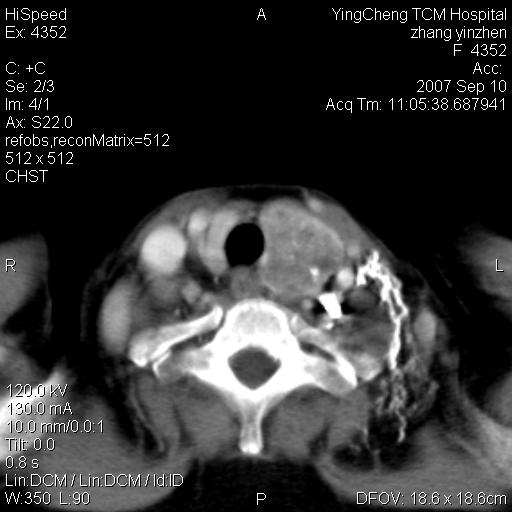

以下是引用卜一在2007-9-18 14:41:00的发言:[br]右肺肿块:毛刺+胸膜凹陷征+供血血管+浅分叶+强化。支持:周围性肺癌 !另:左侧甲状腺腺瘤!

以下是引用夏季在2007-9-18 11:00:00的发言:[br]1。右肺肿块,周围有短毛刺,肺门侧有血管与其相连,胸壁侧有胸膜凹陷征,考虑周围性肺癌 2。左侧甲状腺软组织肿块,内有高密度钙化灶,考虑左侧甲状腺腺瘤。